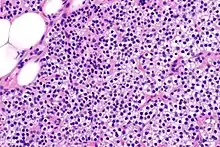

Primary hyperplasia of the parathyroid gland, results from both hypocalcaemia and increased phosphate levels by decreasing expression of calcium sensing receptors and vitamin D receptors at the parathyroid gland.[8][4] These decreases in receptor expression lead to hyperfunctioning of the parathyroid. Hyperfunction of the parathyroid gland is thought to exacerbate primary hyperplasia which evolves further to a secondary more aggressive hyperplasia. Histologically, these hyperplasic glands can be either diffuse or nodular.[24] Primary hyperplasia, usually resulting in diffuse polyclonal growth is manly related to reversible secondary hyperparathyroidism. Secondary hyperplasia of the parathyroid gland is more often a nodular, monoclonal growth that sustains secondary hyperparathyroidism and is the catalyst in the progression to tertiary hyperparathyroidism. Nodular hyperplastic glands in tertiary hyperparathyroidism are distinctly larger in both absolute size and weight up to 20-40-fold increases have been reported.[25][26][24]

Parathyroid glands are normally composed of chief cells, adipocytes and scattered oxyphil cells.[27][14] Chief cells are thought to be responsible for the production, storage and secretion of parathyroid hormone. These cells appear light and dark with a prominent Golgi body and endoplasmic reticulum. In electron micrographs, secretory vesicles can be seen in and around the Golgi and at the cell membrane. These cells also contain prominent cytoplasmic adipose.[27][14] Upon onset of hyperplasia these cells are described as having a nodular pattern with enlargement of protein synthesis machinery such as the endoplasmic reticulum and Golgi. Increased secretory vesicles are seen and decreased intercellular fat is characteristic.[27][24] Oxyphil cells also appear hyperplasic however, these cells are much less prominent.

Biochemically, there are changes in function between normal and nodular hyperplastic parathyroid glands. These changes involve proto-oncogene expression and activation of proliferative pathways while inactivating apoptotic pathways.[28] In nodular parathyroid tissue increased expression of TGF-a, a growth factor, and EGFR, its receptor, results in aggressive proliferation and further downregulation of vitamin D receptors, which act to suppress hormone secretions.[25][8][28] Furthermore, the proliferative marker, Ki67 is seen to be highly expressed in the secondary nodular hyperplastic state.[28][25] Tumour suppressor genes have also been highlighted as being silenced or degraded in nodular hyperplastic parathyroid tissue.[8][28] One such gene, p53, has been shown to regulate multiple tumour suppressor pathways and in tumorigenesis can be degraded by b-catenin. This pathway, in some aspect, is mediated by CACYBP, which is highly expressed in nodular parathyroid hyperplasia.[28]